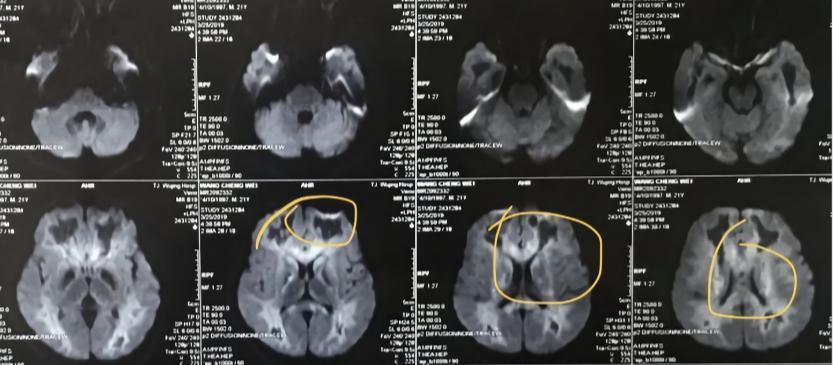

这是一个因一氧化碳中毒缺氧而深度昏迷的病人,他是个植物人。

患者的大脑影像报告

医生翻过一张张病理报告,试图用"不再发电""出现萎缩"等词汇,描述一个至今未被医学完全解锁的世界。医学诊断中,并没有「植物人」这类通俗表达,专业的说法是"慢性意识障碍"。严重的颅脑创伤,大脑缺血缺氧都会导致植物人的出现。